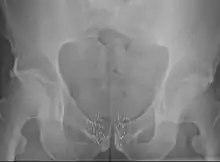

La curiethérapie pour traiter le cancer de la prostate peut être appliquée soit par l'implantation permanente de grains BDD soit par curiethérapie HDD temporaire[19],[59],[60]. L'implantation permanente des grains est adaptée aux patients qui ont une tumeur localisée et de bon pronostics de guérison[8],[59],[61],[62]. Il a été démontré que c'est un traitement très efficace contre la récidive[6],[8]. La taux de survie est similaire à celui observé avec la radiothérapie externe ou la chirurgie (prostatectomie radicale), mais avec moins d'effets secondaires tels que l'impuissance et l'incontinence[14]. La procédure peut être réalisée rapidement. Les patients sont généralement en mesure de rentrer chez eux le jour même du traitement et de retourner à leurs activités normales après 1 à 2 jours[3]. L'implantation permanente de grains est souvent une option moins invasive du traitement par rapport à l'ablation chirurgicale de la prostate[3].

La curiethérapie temporaire HDD est une approche nouvelle pour traiter le cancer de la prostate, mais reste moins fréquemment utilisée, moins fréquente que l'implantation permanente de grains. Cette technique (également appelée boost thérapie) est employée de manière à offrir une dose supplémentaire par rapport à la radiothérapie externe. En effet, elle offre une méthode alternative pour délivrer une dose élevée de radiothérapie adaptée au type de tumeur de la prostate, tout en épargnant les tissus environnants de l'exposition aux rayonnements[9],[10],[60],[61],[11],[63]. La curiethérapie HDD comme amélioration pour le traitement du cancer de la prostate signifie aussi que les séances de radiothérapie externe peuvent être plus courtes que quand la radiothérapie externe est utilisé seule[9],[10],[63],[64].